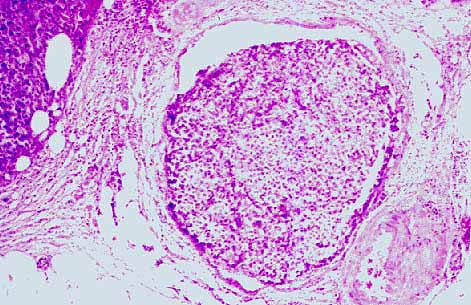

Foto nº 7: Vena ocupada por un trombo tumoral.